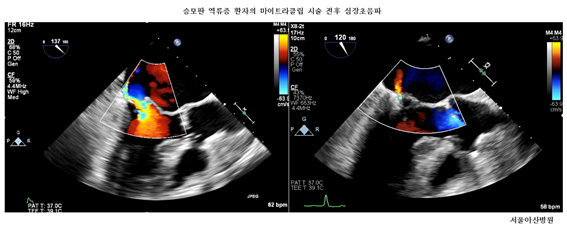

¼­¿ï¾Æ»êº´¿ø "¼ö¼ú ¾Ê°í ÁßÁõ ½Â¸ðÆÇ ¿ª·ùÁõ Ä¡·á"

¹Ú´ö¿ì ±³¼öÆÀ, ù '¸¶ÀÌÆ®¶óŬ¸³ ½Ã¼ú' ¼º°ø¡¤¡¤¡¤FDA ½ÂÀΡ¤½ÅÀÇ·á±â¼ú ÀÎÁ¤

5ÀÏ ¼­¿ï¾Æ»êº´¿øÀº "½ÉÀå³»°ú ¹Ú´ö¿ì·±è´ëÈñ·°­µµÀ± ±³¼öÆÀÀÌ ÃÖ±Ù 82¼¼ °í·ÉÀÇ ³²¼º ȯÀÚ ±è ¸ð¾¾¿¡°Ô ±¹³»¿¡¼­ óÀ½À¸·Î ½Â¸ðÆÇ ¿ª·ùÁõ Ä¡·á¿ë ±â±¸ÀÎ ¸¶ÀÌÆ®¶óŬ¸³(Mitraclip) ½Ã¼úÀ» ¼º°øÀûÀ¸·Î ½ÃÇàÇß´Ù"°í ¹àÇû´Ù.

¼­¿ï¾Æ»êº´¿ø ½ÉÀ庴¿ø ÅëÇÕÁø·áÆÀÀº °íÀ§Ç豺 ȯÀÚÀÎ ±è ¾¾°¡ º¸´Ù ¾ÈÀüÇÏ°Ô Ä¡·á¹ÞÀ» ¼ö ÀÖµµ·Ï °³Èä¼ö¼ú ¾øÀÌ ¸¶ÀÌÆ®¶óŬ¸³ 2°³¸¦ ½Â¸ðÆÇ¿¡ ½Ã¼ú, ½Â¸ðÆÇ ¿ª·ùÁõÀ» Ä¡·áÇß´Ù. ÀÌ ½Ã¼úÀº È¸º¹±â°£µµ ª¾Æ ±è ¾¾´Â ½Ã¼ú 5ÀÏ ÈÄ Åð¿øÇß´Ù.

¸¶ÀÌÆ®¶óŬ¸³Àº ½Â¸ðÆÇ¸·À» ±¸¼ºÇÏ´Â µÎ °³ÀÇ ÆÇ »çÀ̸¦ Ŭ¸³Ã³·³ Áý¾î¼­ ÆÇ¸·ÀÌ ¿­¸®°í ´ÝÈú ¶§¸¶´Ù »ý±â´Â ºóÆ´À» ¾ø¾Ö Ç÷¾× ¿ª·ù¸¦ °¨¼Ò½ÃŰ´Â ±â±¸´Ù. °³Èä¼ö¼ú ¾øÀÌ »çŸ±¸´Ï Á¤¸ÆÀ» ÅëÇØ °¡´À´Ù¶õ °üÀ» ³Ö¾î ½ÉÀå ³»ºÎ¿¡ µµ´ÞÇÑ ÈÄ ½Â¸ðÆÇ¿¡ Ŭ¸³À» ÀåÂøÇÑ´Ù.

±è´ëÈñ ¼­¿ï¾Æ»êº´¿ø ½ÉÀå³»°ú ±³¼öµµ “¸¶ÀÌÆ®¶óŬ¸³ ½Ã¼úÀº 3D ÃÊÀ½ÆÄ·Î Ŭ¸³ÀÇ Á¤È®ÇÑ À§Ä¡¿Í ½Â¸ðÆÇÀÇ ÇØºÎÇÐÀû ±¸Á¶¸¦ ½Ç½Ã°£ È®ÀÎÇϸ鼭 ÁøÇàÇϱ⠶§¹®¿¡ ÀÇ·áÁø °£ ±ä¹ÐÇÑ ÇùÁøÀÌ ÇʼöÀûÀÌ´Ù"¸ç "¾ÕÀ¸·Îµµ ȯÀÚ »óŸ¦ ÃæºÐÈ÷ °í·ÁÇÑ ¸ÂÃãÇü ½Ã¼ú·Î ȯÀÚµé »îÀÇ ÁúÀ» ³ôÀÏ ¼ö ÀÖµµ·Ï ÃÖ´ëÇÑ ³ë·ÂÇÒ °Í”À̶ó°í ÀüÇß´Ù.